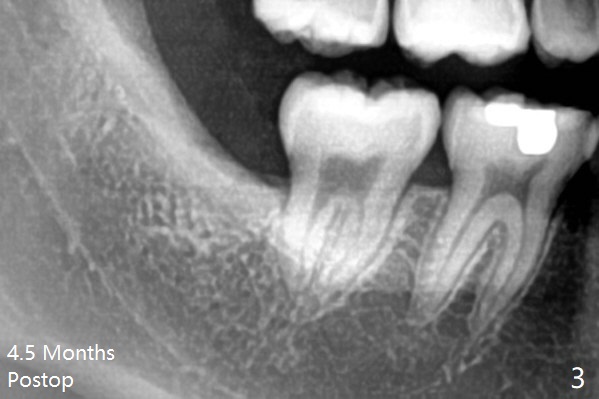

A 19-year-old man with history of orthodontic treatment (Fig.1,2) returns to office for #1,16,17,32 extraction with Collagen Plug placement at #17 and 32 (4-0 plain gut suture). The sockets heal in 4.5 months (Fig.3).